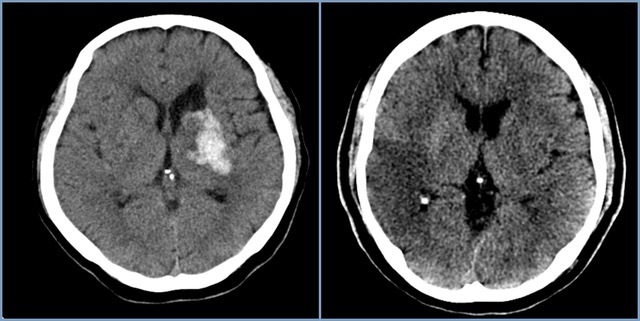

뇌경색 치료 방법

뇌경색 초기증상이 의심된다면 지금 바로 병원을 내방해 진단을 받고 적절한 치료를 손대는 것이 후유증을 감하는데 중요 해요. 시간이 관건이며, 뇌세포의 괴사, 증상 악화, 너무 늦으면 사망에 이를 수 있는 뇌혈관의 괴사를 피하기 위하여 증상이 나타난 뒤에 4시간 이내에 잘 맞은 약물, 시술 또는 수술을 신속히 실시해야 합니다. 치료로 즉시 하셔야 해요.